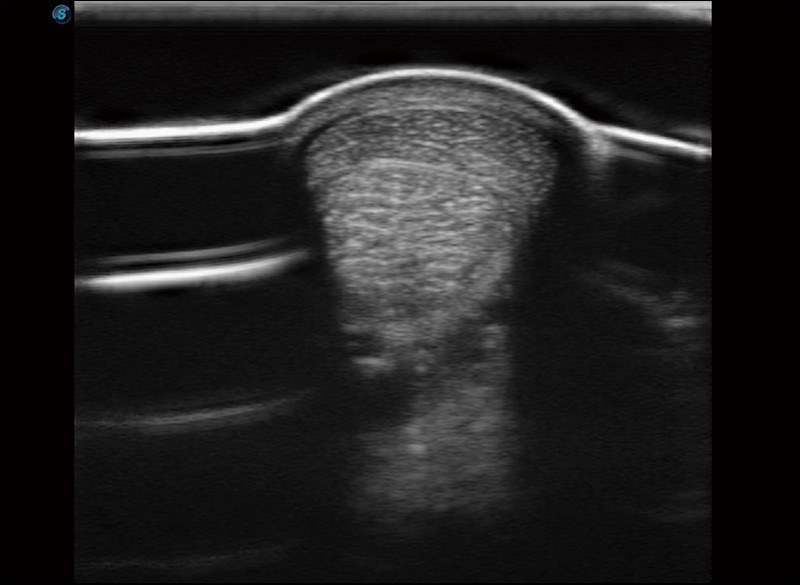

α1卓越的图像质量和便捷的工作流程,使每位宠物医生都能轻松扫查。其全面的兽用应用功能和紧凑型的结构设计,可以满足动物检查的多种需要。专业的预设检查模式和多领域测量软件包有助于为不同类型的动物提供检查, 让宠物医生能够出色的完成工作。

任意波束合成技术

在不牺牲时间分辨率的情况下提供出色的图像